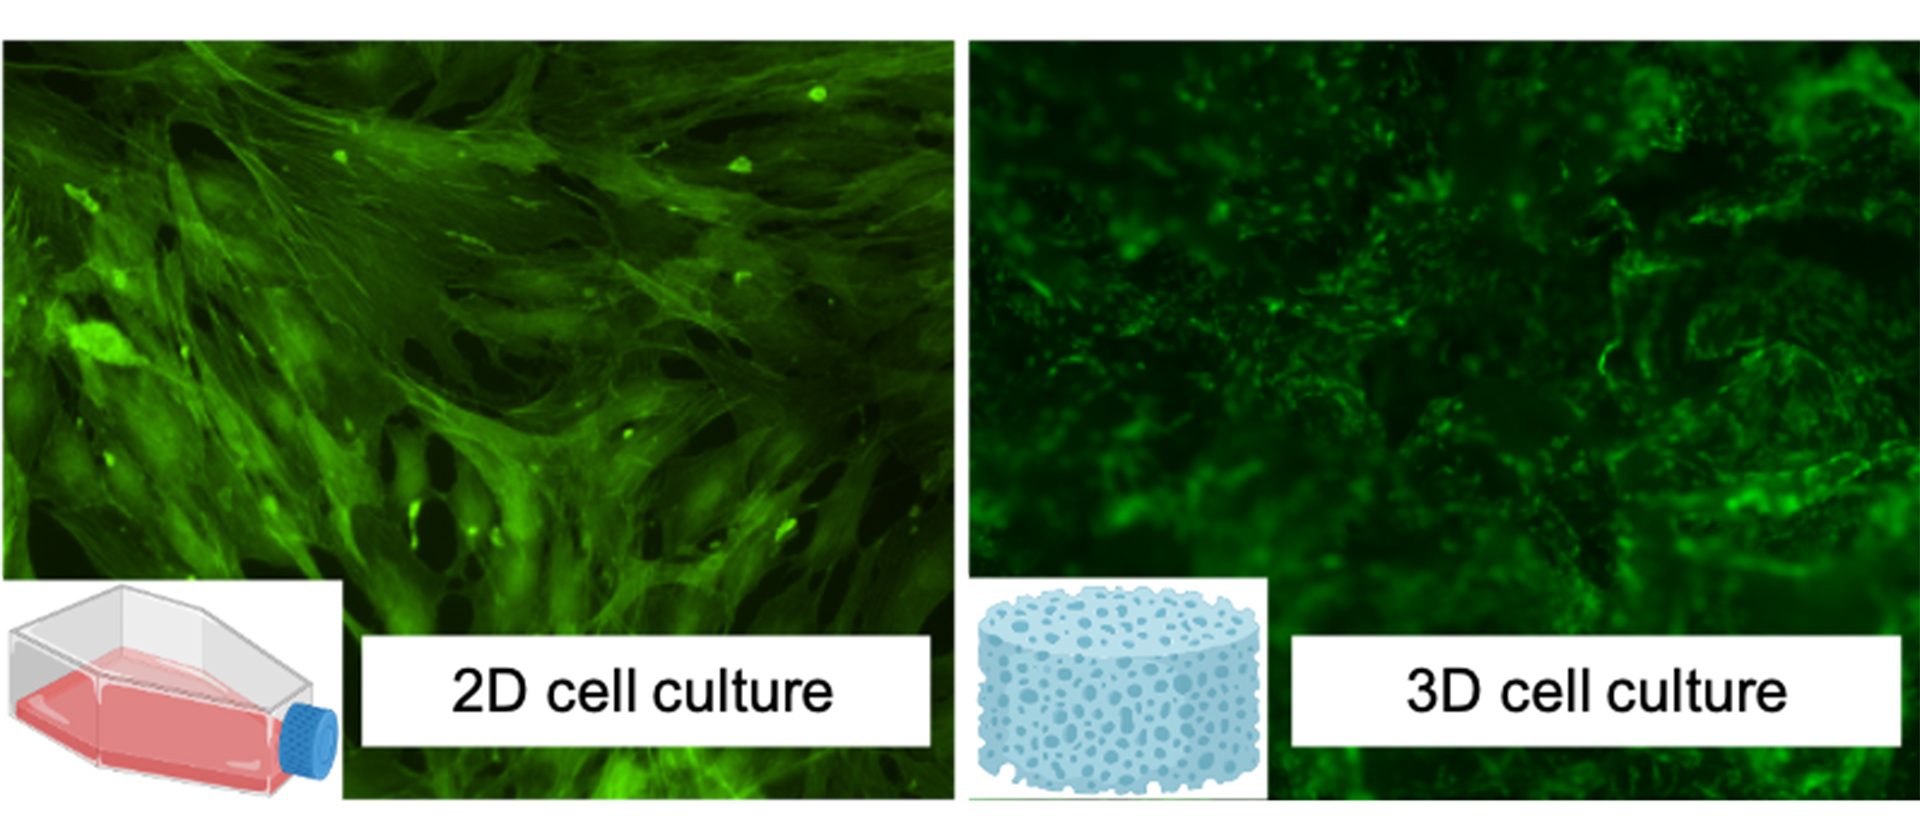

The project applies the experimental activity to osteosarcomas, a particular type of bone cancer that affects adolescents, and two other main categories of tumours with high incidence and morbidity worldwide (breast and brain). After an initial screening using standard in vitro tests where cytotoxicity and bioactivity of new systems have been evaluated, CNR is now moving to more complex cell culture models. Bidimensional (2D) culture systems still represent the gold standard models for in vitro research as simple, cost-effective, robust, and an excellent high-throughput practice option for cell-based biology studies.

Unfortunately, these systems are not able to recapitulate in vivo three-dimensional (3D) environments, resulting in a poor in vitro–in vivo translation, as shown in Fig. 2. In addition, differences in intra-species limited the use of animal data for predicting human responses, increasing in vivo preclinical failures and ethical concerns. Dealing with these challenges, in vitro 3D technological approaches were recently bioengineered as promising platforms able to closely capture the complexity of in vivo normal/pathological tissues.

In the Nano4Tarmed project, CNR, thanks to biomaterials (i.e., collagen-based scaffolds), is carrying out innovative three-dimensional tests to test the effectiveness of drug delivery. These studies provide:

- Optimal and promising platforms to closely capture in vivo microenvironment in a laboratory setting;

- Seal the gap between the 2D culture systems and animal models;

- Improve test outcomes; and

- Decrease the use of animals for in vivo studies.